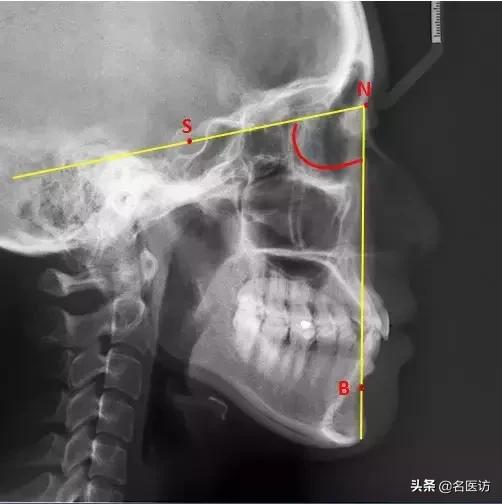

3、U1-SN

U1:上中切牙切缘点

反映上中切牙(俗称门牙)相对于颅底的倾斜度,角度越大,门牙越突,也就越可能出现龅牙的侧貌。